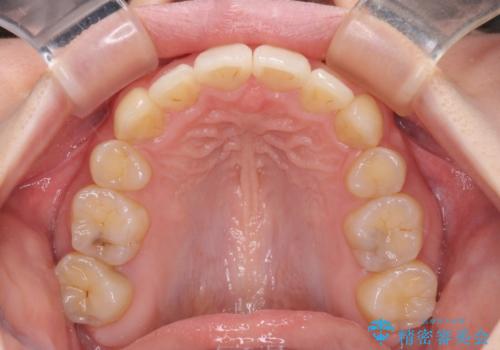

その後スペースを閉じるために時間を要しましたが、満足のいく仕上がりとなりました。

- 2年10ヶ月

- 10-30回